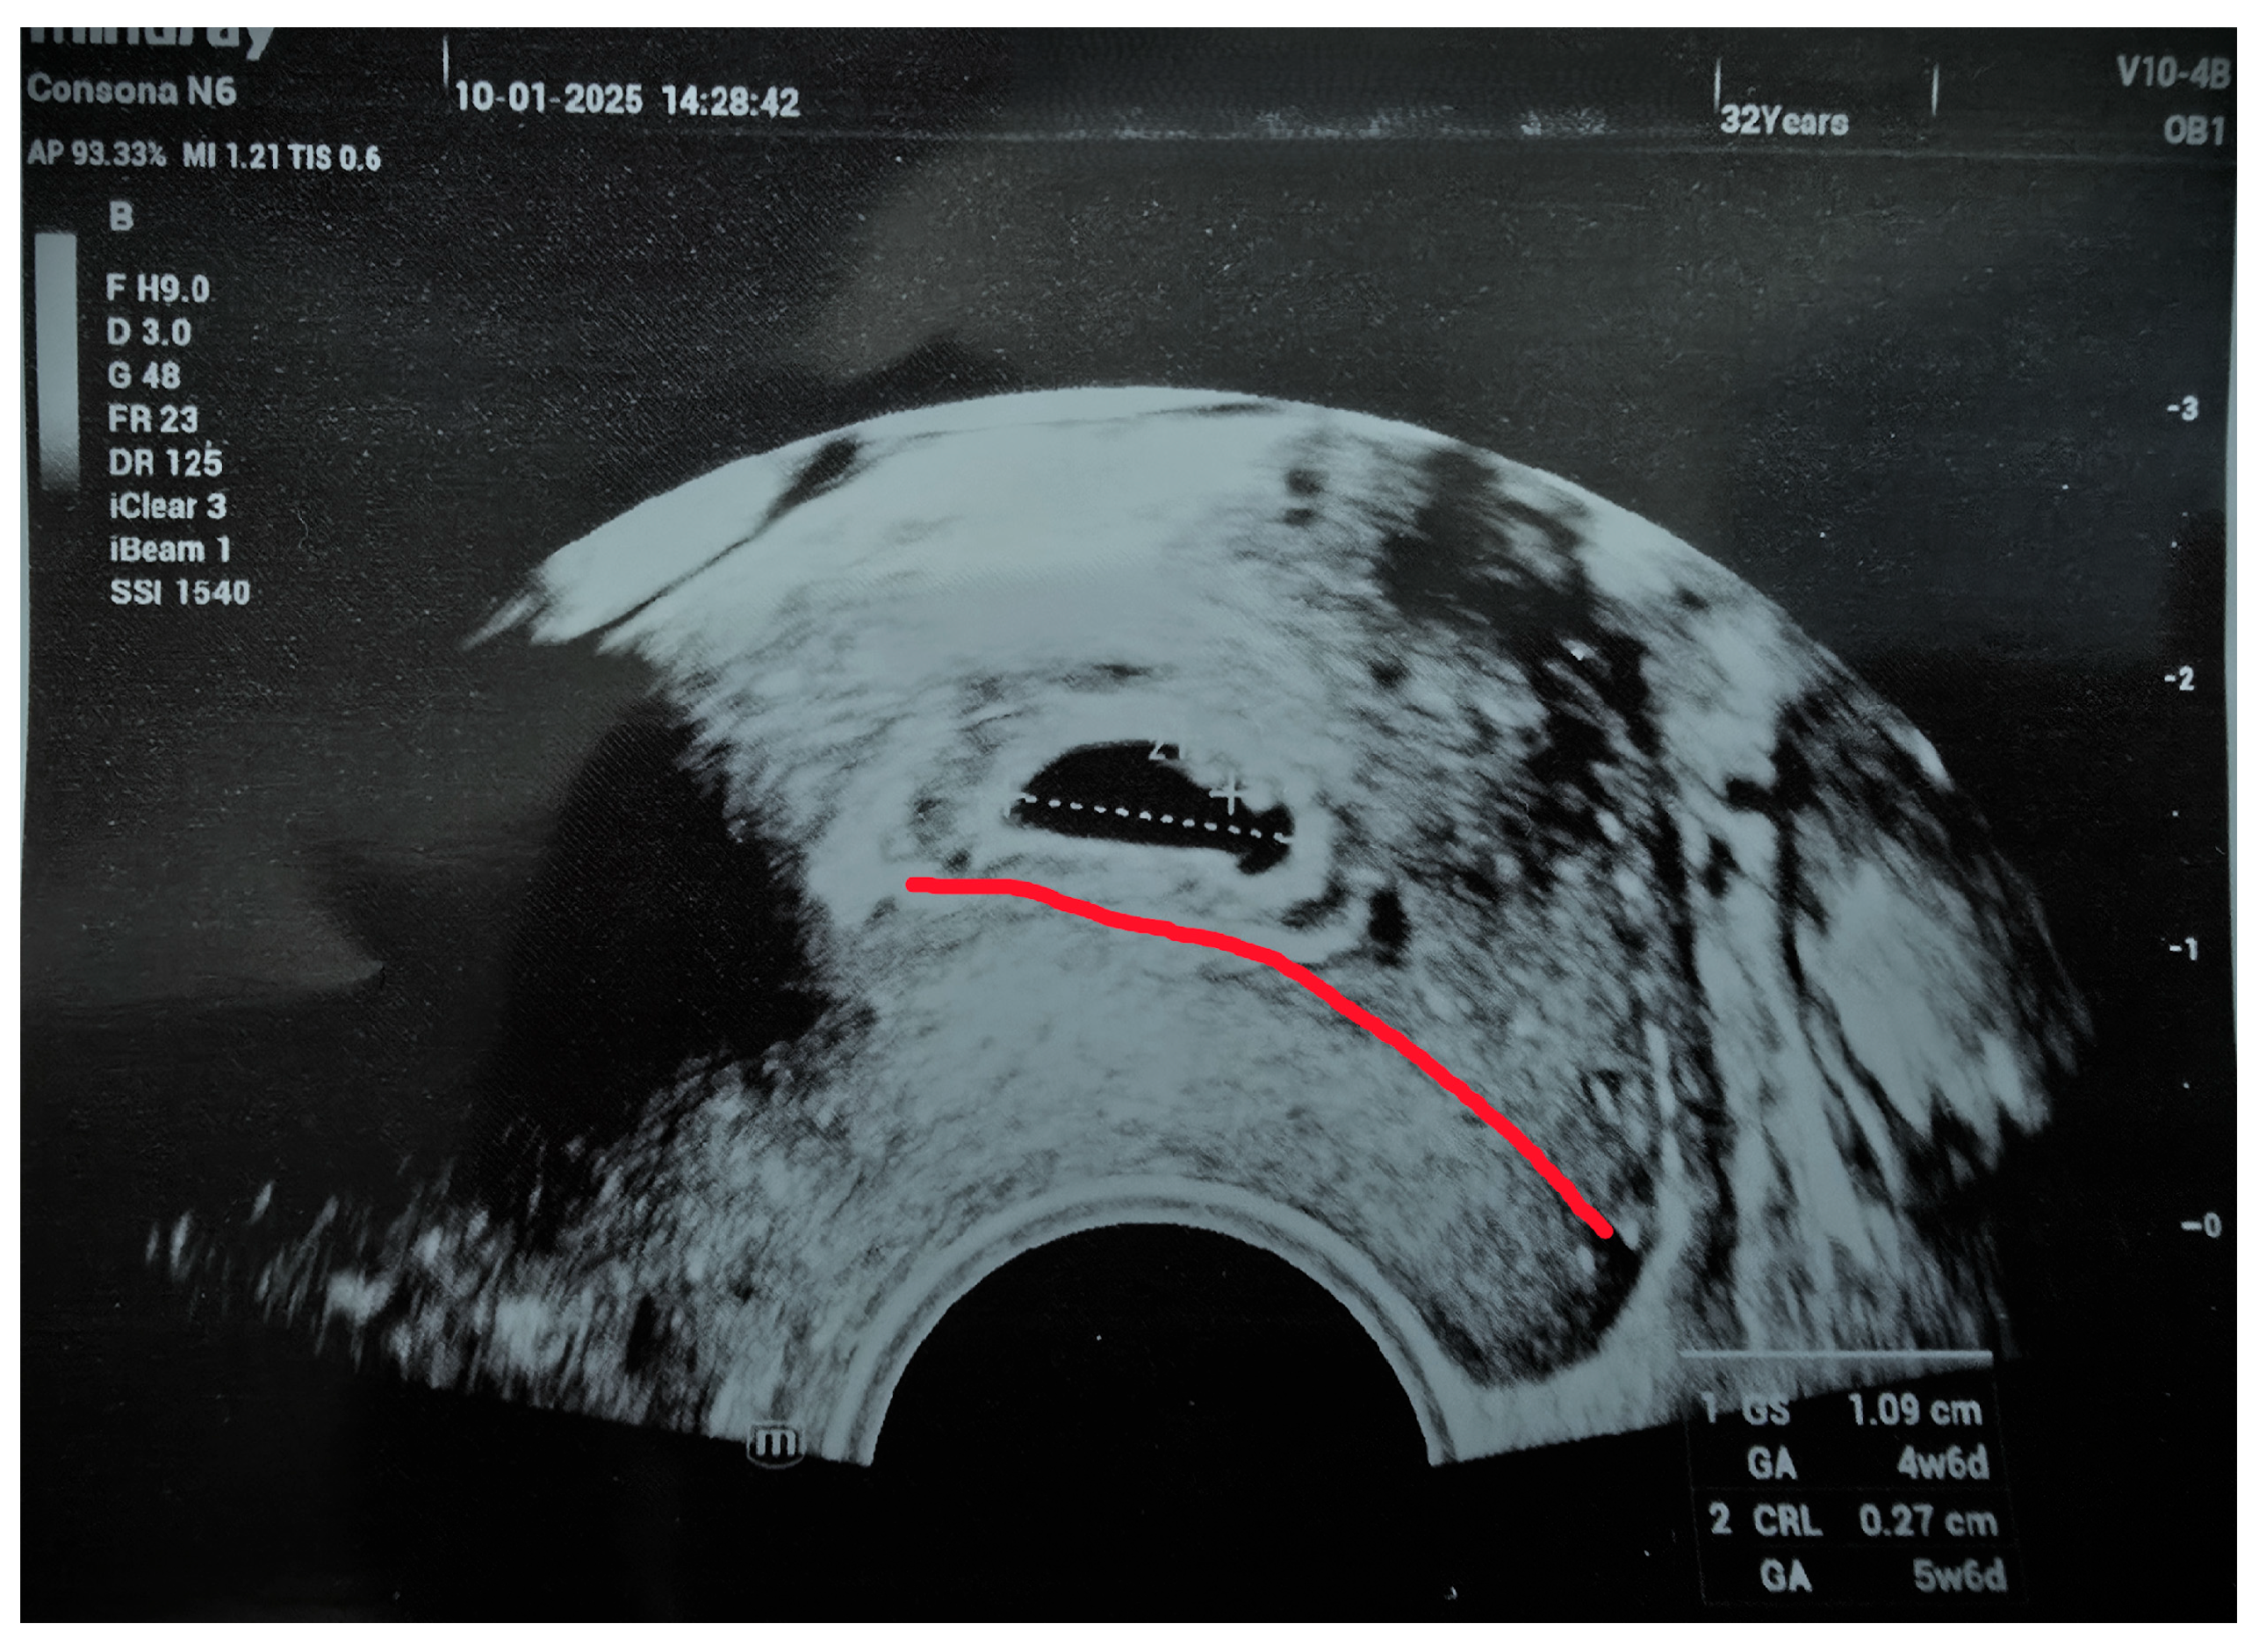

2. Case Report